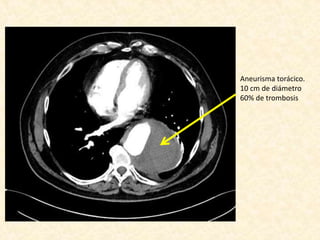

• Leve dilatación de arco aórtico

• La aorta descendente se presenta elongada, tortuosa y

presenta un gran aneurisma que compromete gran

parte de su extensión, el cual se inicia

aproximadamente 6 cm del origen de la subclavia

izquierda, se extiende por aproximadamente 15 cm, y

alcanza un diámetro máximo de 10 cm, con trombosis

aproximadamente del 60% de la luz.

Aneurisma torácico.

10 cm de diámetro

60% de trombosis

Informe • Leve dilataciónde arco aórtico • La aorta descendente se presenta elongada, tortuosa y presenta un gran aneurisma que compromete gran parte de su extensión, el cual se inicia aproximadamente 6 cm del origen de la subclavia izquierda, se extiende por aproximadamente 15 cm, y alcanza un diámetro máximo de 10 cm, con trombosis aproximadamente del 60% de la luz. • La aorta abdominal es tortuosa, con ateroma severo de predominio de placas no calcificadas, sin aneurismas. • Estenosis crítica de la arteria renal derecha • Riñones levementes asimétricos por menor tamaño del derecho